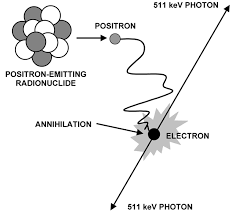

What type of energy interaction does a PET camera pick up on?

Picks up on the energy emitted from an annihilation interaction between an electron and a positron that’s lost energy – positively charged electron

Is a byproduct of beta positive decay

Can you elaborate on how beta positive decay works or takes place? (type of parent, what happens in the nucleus, and what happens to the byproduct)

The parent is unstable and has too many protons → will convert one of the protons into a neutron

As consequence of this conversion, it will create a positron as a byproduct that will get ejected from the nucleus

The positron will travel a length of distance – losing energy until it becomes a positively charged electron

It will then interact with a negatively charged electron and cause an annihilation reaction

How many photons are made during an annihilation reaction?

2 photons are emitted – one is equal to 511 keV

What is the total energy made when an annihilation reaction occurs?

1.02 MeV – 511 keV + 511 keV

What needs to take place before an annihilation reaction happens?

The positron needs to have reached its rest mass – or else the photons made would be more than 511 keV